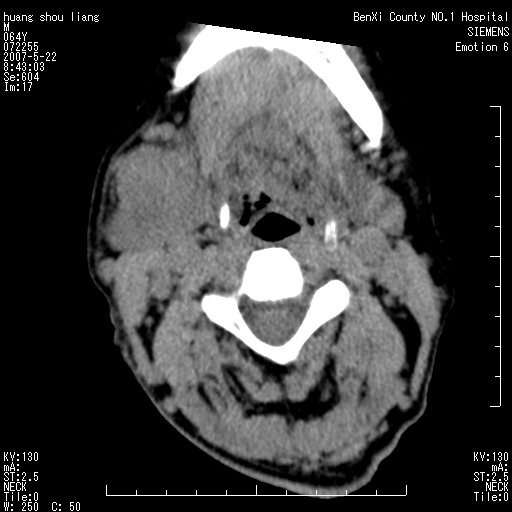

男性,64岁。颈部包块8年。最近增大。

对不起大家,可能是片子发太多有点乱,正常腮腺在下颌角的外侧,颌下腺在下颌体的中部内侧,本例在下颌角内侧偏下,和腺体一点关系都没有,从vrt和mpr上可以很明显看出来,再者肿块是好多粘连在一块的,大家在仔细看看,左侧可能也是吧,我还是考虑为肿大的淋巴结融合在一块,但性质??????

右侧腮腺下部均匀软组织密度肿块,外形不规则,与周围组织分界清晰,考虑右侧腮腺混合瘤或多形性腺瘤。

大家好,病理结果出来了,如大家所说,颌下腺混合瘤。

唉,解剖没学好吧,我诊断错了,不过还是有些不理解回去我在多看看书,谢谢大家的参与,以后我还会奉献好的病例。